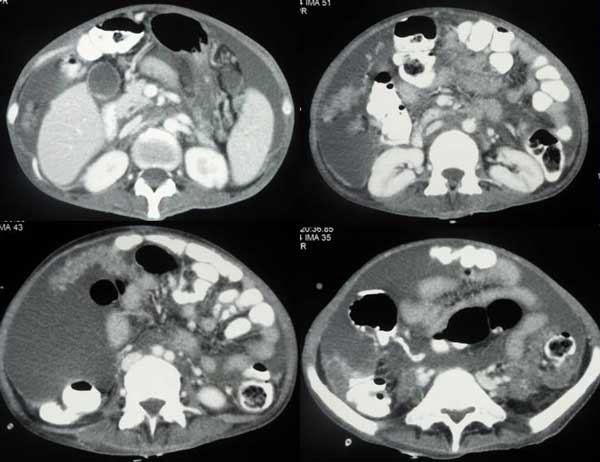

Tag (not real name) was a 59-year-old man from Indonesia. In April 2011, he had coughs with itchy throat. He went to see his doctors and was give medication but these did not help. In August 2011, he came to Penang for further consultation. A CT scan on 22 August 2011 showed an irregular mass (6.6 x 8.0 cm) in the upper left lung extending to the pulmonary hilum with left hilar and mediastinal adenopathy. He also complained of pain in the left pelvis. MRI done on 6 September 2011 showed lesion at the body of C6, body and left pedicle of the L5 vertebra. This was probably metastatic in nature. The doctor said Tag had a Stage 4 cancer.

Re-examination of his chest CT scan showed his lung tumour had increased in size. Tag went to China for further treatment in October 2011. In China Tag underwent a biopsy again. The cancer was again confirmed as a poorly differentiated adenocarcinoma. Tag underwent the following treatments in China:

In the meantime while in the hospital, Tag’s wife came to CA Care and asked for our opinion. The following are the images of his CT and PET scans.